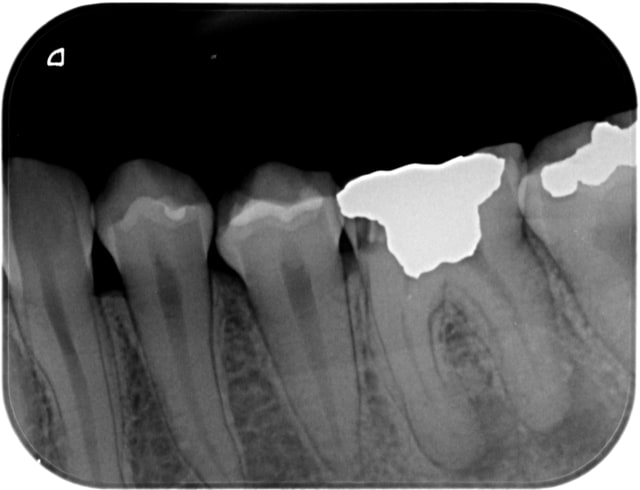

Un p'tit exemple ce matin, d'une assurée sociale française qui vient au cab en urgence, assurée qui cotise le plus de tous les assurés des pays de l'OCDE... Elle reçoit donc des traitements à la pointe de la technologie en accord avec les données acquises de la science.

Ci joint, la radio de la jeune assurée française qui a reçu les soins du meilleur système de santé au monde !!!

(et ça c'est la fournée de ce matin... et que de ce matin).